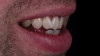

(13.) Case 1: Full-smile view of the definitive all-ceramic restoration on the maxillary right central incisor.

Figure 13

Eight weeks after the initial start of the walking bleach procedure, the final layered lithium disilicate crown was tried-in and evaluated for function and esthetics. Upon patient approval, the intaglio surface of the crown was etched for 20 seconds with a 9.6% hydrofluoric acid etchant, rinsed, and then scrubbed with a 37.5% orthophosphoric acid solution to clean out any ceramic debris. The crown was then placed into an ultrasonic bath of 91% isopropyl alcohol for 5 minutes, after which the intaglio surface was coated with silane and placed under a warm air dryer for 1 minute. A translucent self-adhesive resin cement was used to bond the final restoration to the preparation. The patients both stated that they approved of the form, function, and esthetics of the definitive restoration and that they were very pleased with the final results (Figure 13 through Figure 18). Routine periodic evaluations and radiographs were scheduled to monitor their oral health and esthetics.